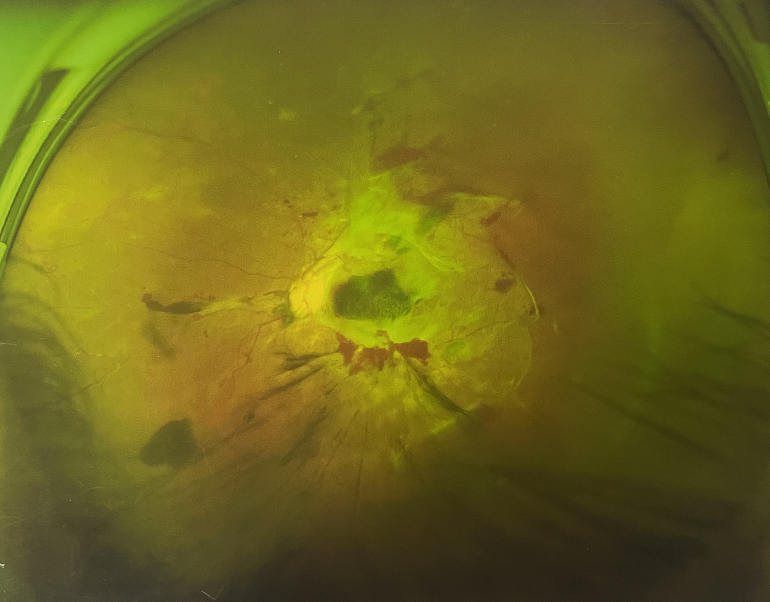

左眼發(fā)展到糖尿病視網(wǎng)膜病變VI期

由于王女士的左眼沒有聽從醫(yī)生盡快做手術(shù)的建議,一直耽誤,從4月前的0.4視力逐漸下降到僅剩眼前手動,導(dǎo)致左眼發(fā)展到糖尿病視網(wǎng)膜病變VI期(屬于6期糖網(wǎng)中的晚期),已經(jīng)產(chǎn)生大量新生血管+纖維增值+廣泛牽拉性視網(wǎng)膜脫離,由于耽誤了病情,且病情發(fā)展異常迅速,導(dǎo)致目前左眼連保住眼球都很困難。

“而如果4月余前,左眼及時手術(shù)(當(dāng)時左眼病情比右眼輕,增殖膜還未累及黃斑),左眼將恢復(fù)的比右眼還好,甚至可以恢復(fù)到0.8或1.0,而現(xiàn)在連保住眼球的機(jī)會都很渺茫”,張小虎醫(yī)生表示實(shí)在可惜。

4個月前的左眼